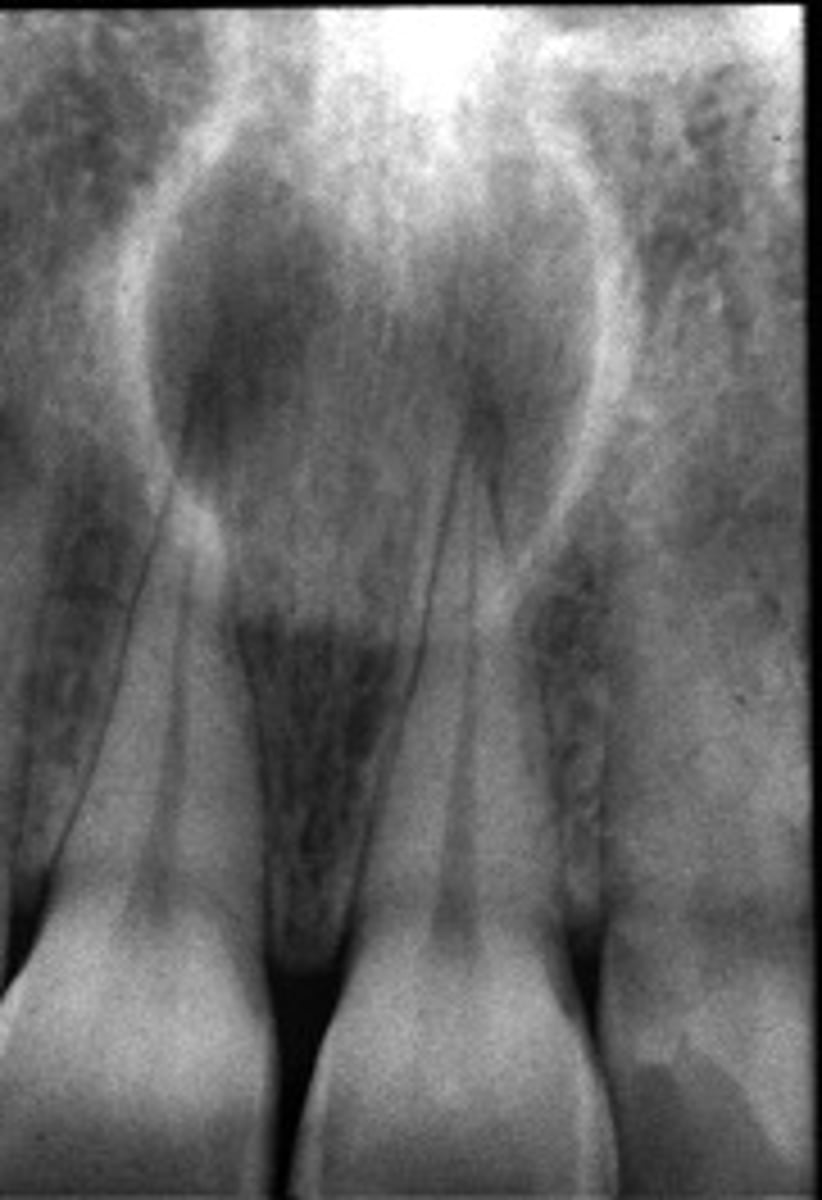

how would you describe this lesion?

A. well-defined, periapical radiolucent lesion associated with #24 and 25

B. ill-defined, periapical radiolucent lesion associated with #24 and 25

C. well- defined, multilocular periapical lesion associated with tooth number 24 and 25

D. mixed density, periapical lesion associated with teeth number 24 and 25

- Also note loss of apical lamina dura of 24, 25

What category would this lesion be part of?

Dysplasia

What would be a differential diagnosis for this lesion?

PCOD (stage 1)